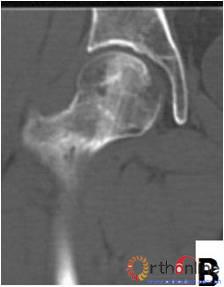

图2-3

图2 依据股骨头外侧柱存留情况,股骨头坏死的分型。(图2-1)分为Ⅰ型(外侧柱全部存留)(A)MRI图像显示;(B)7年后CT显示股骨头仍未塌陷;(图2-2)Ⅱ型(外侧柱部分保留)(A)MRI显示外侧皮质存留;(B)4年后CT显示股骨头仍未塌陷;(图2-3)Ⅲ型(坏死带穿透股骨头);(A)MRI显示坏死带;(B)2年后股骨头塌陷

Fig 2 According to preservation of the lateral pillar, the necrosis was divided into three types. (Fig 2-1)Type Ⅰ: Whole lateral pillar preserved (A) MRI showing; (B) no collapse occurred seven years later by CT showing. (Fig 2-2)Type Ⅱ: Preservation of the partial lateral pillar, (A) MRI showed the preservation of the lateral cortical bone; (B) no collapse of the femoral head four years by CT. (Fig 2-3)Type Ⅲ: the necrotic line pass through the cortical bone and bone morrow ;(A) MRI showed the necrotic line; (B) collapse of the femoral head occurred two year later.